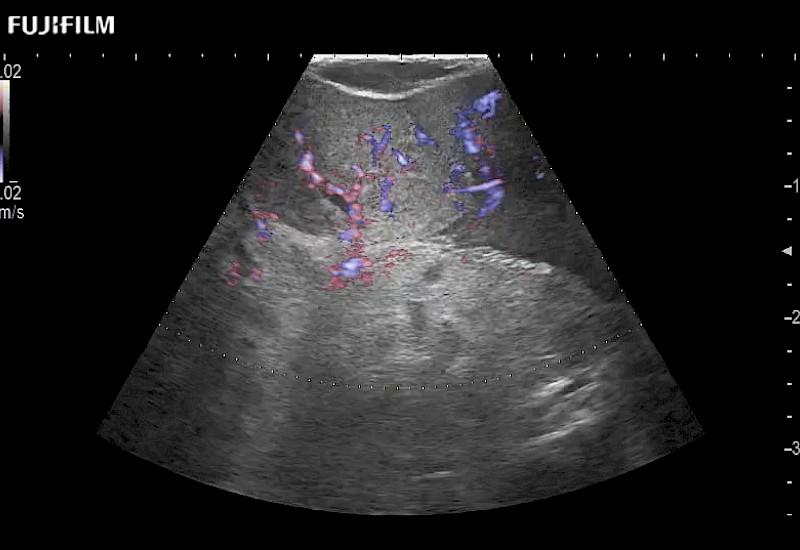

for use during robotic, laparoscopic and open surgical procedures: Tumor localization & staging, Ablation, Resection, Biopsy, Transplant, Abdominal exploration, Microsurgery

Our dedication to Robotic Surgery allows us to offer superior image quality, outstanding system reliability and intuitive use of cutting edge technology.

The ARIETTA 750 incorporates all of the proven technologies and functions that medical professionals have come to expect from Fujifilm Healthcare.

ARIETTA 750 is the definitive diagnostic ultrasound solution for any clinical setting - Private Office, Imaging Center, or Hospital. The ARIETTA platform provides the ultimate in clinical performance with its state-of-the-art features and large user-friendly display.

The ARIETTA 650 DI combines trusted Fujifilm Healthcare technologies and features tailored for surgical oncology.

Designed to meet the demands of surgeons, the ARIETTA 650 DI offers precise guidance. Its advanced capabilities and large, intuitive display offer accurate and efficient care in operating rooms and specialized surgical settings.